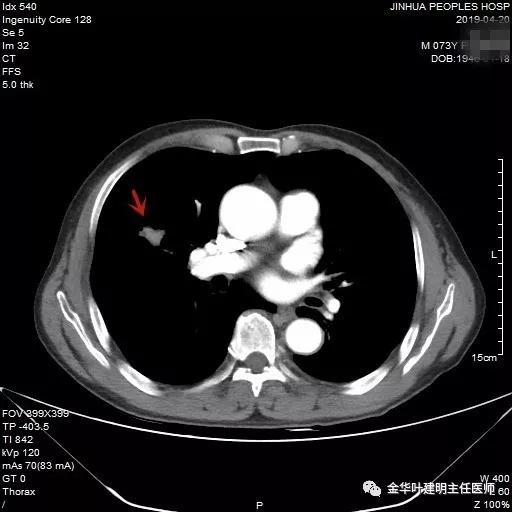

近日,同事再联系了我,说他同村的吴某已经决定来院接受手术治疗。所以就再次收住入院,予以复查了胸部CT增强,结果如下:

病灶较前有进展,更加膨隆了,直径也有所增加,好在仍未见明显纵隔淋巴结转移(特别肿大的淋巴结,但没有查PET评估)。其肺功能评估情况如下: